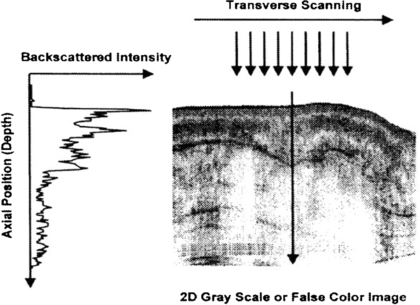

OCT is based on interferometry i.e. the interference between reflected light and a reference beam, which is used as a coherence gate to isolate light from specific depths. A Michelson interferometer is often used to perform the low-coherence interferometry for OCT (Fujimoto et al 2000). The frame rate for early OCT systems was typically 4 to 8 fps but faster modern systems are available at beyond video frame rate (depending on imaging parameters). A schematic representation of an OCT system is shown in figure 19 and example OCT B-mode image in figure 20.

Standard image High-resolution imageFigure 20. Example OCT B-mode scan of tissue formed from a sequence of axial line (A-) scans. Cross-sectional images are constructed by performing measurements of the echo time delay of light at different transverse positions. The result is a two-dimensional data set which represents the backscattering in a cross-sectional plane of the tissue. This data can be displayed as a grayscale or false colour image (permission granted to re-use from Fujimoto et al 2000 Neoplasia 2 9–25, copyright Elsevier). A sequential series of these B-mode images across the tissue can be combined to form a 3D image.